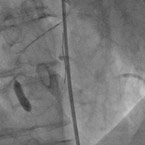

Verengung der rechten Kranzaterie